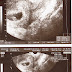

My Second Visit to my Ob-Gyne

I just visited my OB last July 30 for my second Transvaginal U/S. We just hear my baby’s heartbeat for the first time, I am so happy that ...